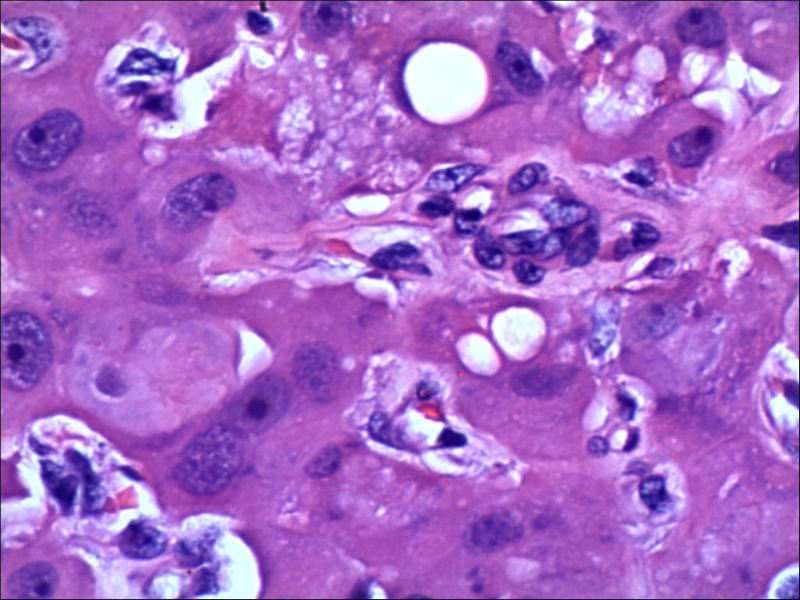

女,27岁,送检右侧卵巢肿物(另外还送检左侧卵巢肿物,大体及镜下显示为畸胎瘤),卵圆形,大小2×1×1cm,似有包膜。卵巢肿物图1

卵巢畸胎瘤中正常卵巢的黄体组织,铺砖样排列,胞浆宽大,较典型。

不好意思,可能是我没说清楚,患者对侧卵巢是畸胎瘤,不是同一侧的,我初步考虑门细胞瘤,图21,22,24,25,26中央的一些细胞是不是很像门细胞

谢谢大家的回答和解疑,忘记一个重要的病史,就是该女性为产妇。但是妊娠黄体瘤与类固醇细胞瘤怎么鉴别呢

那应该是妊娠黄体/黄体瘤,类固醇细胞瘤有嗜酸细胞和组织细胞样细胞两种,此例显然不是。